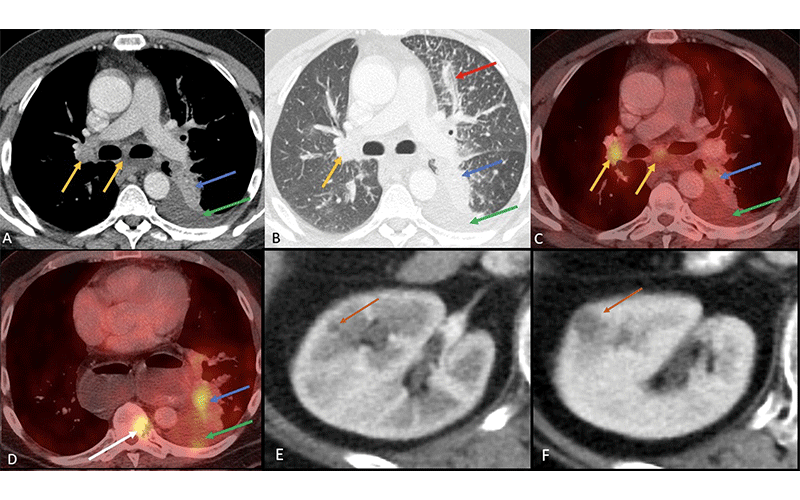

ALK mutation in non–small cell lung cancer. Axial images from (A, B) soft-tissue and lung window CT, (C, D) fusion PET/CT, and (E, F) postintravenous contrast CT of right kidney. Patient is a 53-year-old female who does not smoke, with non–small cell lung cancer with an ALK mutation who presented with (A–D) a central solid fluorodeoxyglucose-avid tumor (blue arrow) accompanied by pleural effusion (green arrow), metastatic mediastinal and hilar lymphadenopathy (yellow arrows), pulmonary lymphangitic carcinomatosis (red arrow in B) and vertebral bone metastasis (white arrow in D). Patients treated with crizotinib (ALK and ROS1 inhibitor) often develop new or increased renal cysts (orange arrow in E, F) with simple or complicated features as part of their treatment. These cysts often regress after stopping crizotinib. https://doi.org/10.1148/rycan.220153 ©RSNA 2023